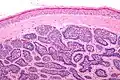

Dermal cylindromas are:

- Dermal lesions consisting of nests of cells that are surrounded by hyaline (i.e., glassy, eosinophilic, acellular) material and have:

- Hyperchromatic nuclei that may palisade (columnar nuclei arranged around the periphery of the cell nests with their short axis tangential to the nest periphery), and

- Cells with lighter staining ovoid nuclei at their centre.

They lack of a significant number of lymphocytes; this differentiates them from spiradenomas.

Micrograph of a dermal cylindroma in H&E stain. -